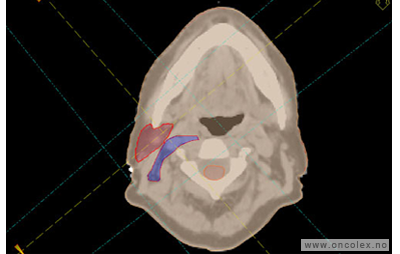

Målvolum

Skisse over hvordan strålefeltet planlegges:

• GTV (Gross Tumor Volume): Identifisert tumor.

• CTV (Clinical Target Volume) GTV + omkringliggende vev hvor det kan væremikroskopisk spredning.

• ITV (Internal Target Volume): CTV + en indre margin som tar hensyn tilindre bevegelser og endringer av CTV.

• PTV (Planning Target Volume): Innstillingsmargin som inneholder ITV og samtidig tar hensyn til antatte pasientbevegelser, samt variasjoner i pasientopplegging og feltinnstillinger.

• Feltgrense. Tegnes som oftest på kroppen.

ICRU (International Commission on Radiation Units and Measurements)